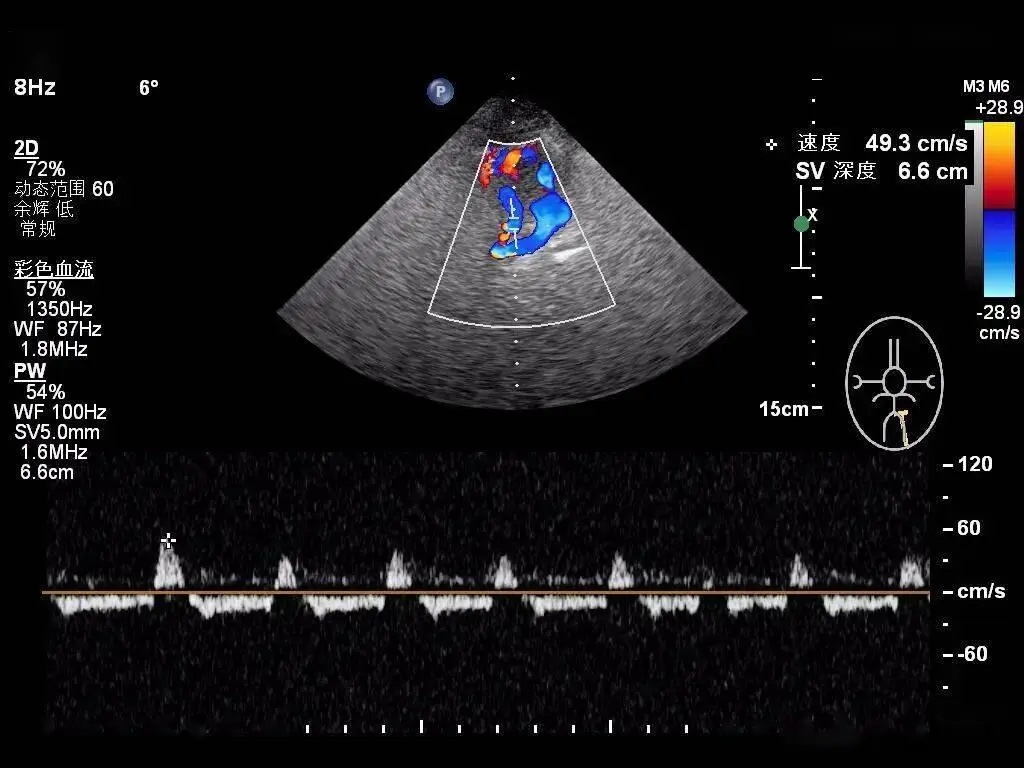

经颞窗平面检查:wills环的彩色血流

经枕骨大孔平面检查:双侧椎动脉与基底动脉彩色血流成像